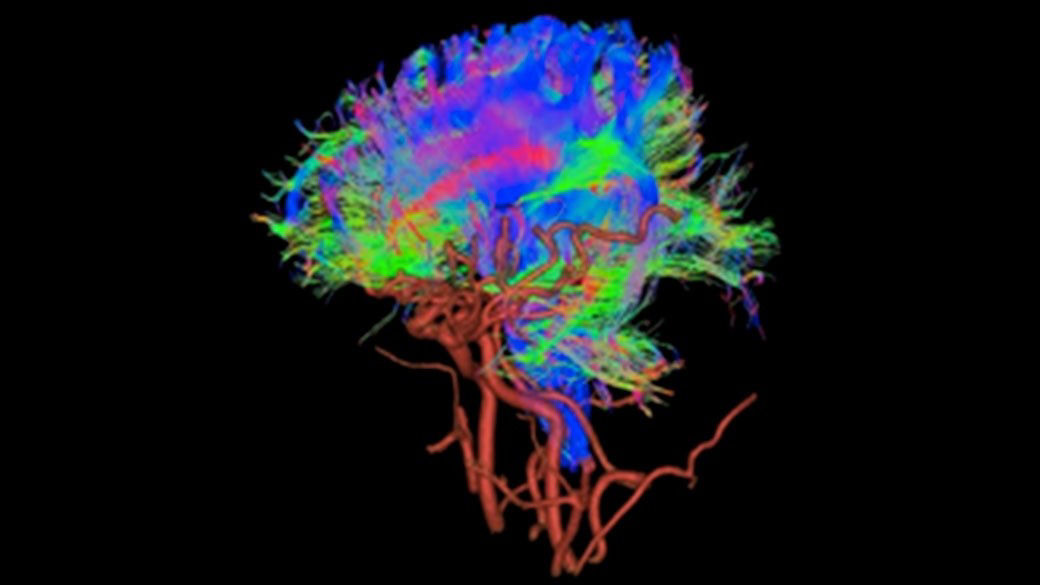

Now it's possible to acquire very small slice thickness of the brain in fetal imaging.

Luca Russo MD

Policlinico Universitario Fondazione Agostino Gemelli, Italy

Achieve a 25% efficiency gain with Ultra High Efficiency (UHE) gradient system. Fast, clear Total Digital Imaging (TDI) increases SNR by 25%. Improved IQ in 80% of cases without added time. Acquire higher SNR without a time penalty and get images virtually free of artifact with AIR™ Recon DL.***